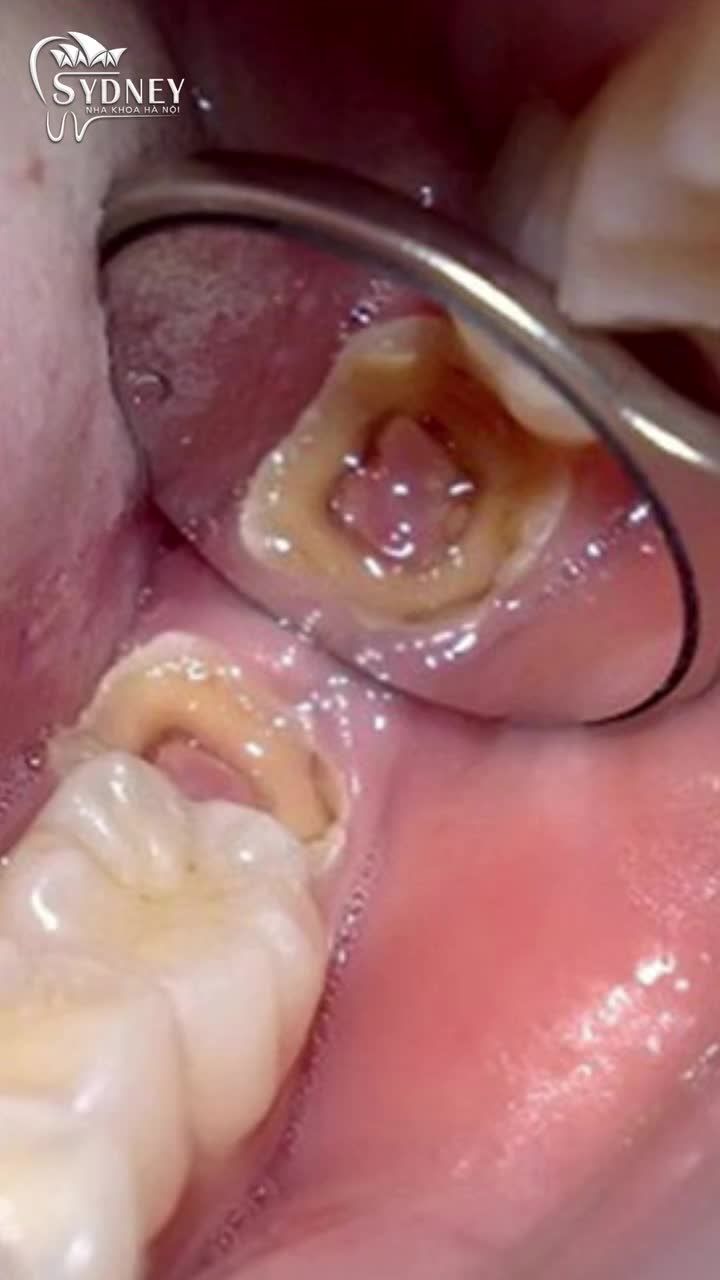

MÔ PHỎNG QUÁ TRÌNH HÀN RĂNG SÂU BĂNG COMPOSITE

SÂU RĂNG VỚI LỖ SÂU LỚN, MẤT NHIỀU MÔ RĂNG